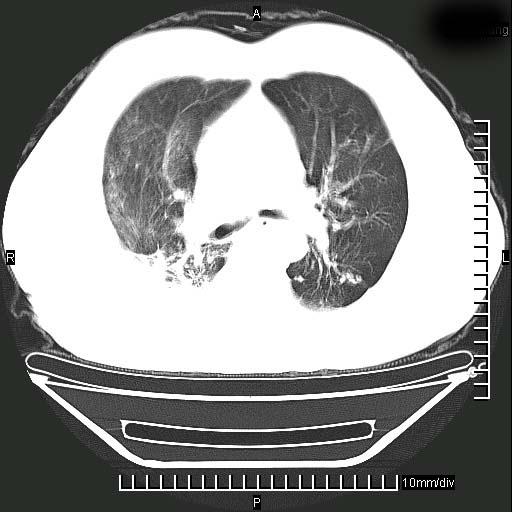

既往肺结核,近10几天,咳嗽,咳痰,右侧胸痛,疼痛较明显,右上肺斑块考虑结核灶胸膜粘连,增强,可惜动脉期没有定好,未见强化,可延迟4分后又见较明显强化,中心见低密度影,如果说结核是边缘强化,可这个灶强化的面积挺大的,让人很挠头。

延迟4分后

1)两肺继发性肺结核。2)右侧胸膜增厚+少量胸腔积液。